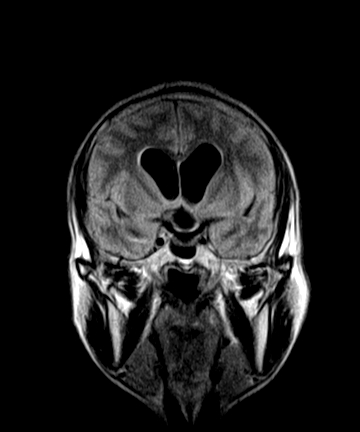

标题: MRI2064:少见病例。男性52,视力下降多年。 [打印本页]

标题: MRI2064:少见病例。男性52,视力下降多年。

四脑室区见混杂信号占位影,脑室系统扩张明显,临近结构显著受压称位,患者52岁,多考虑室管膜瘤可能性大

考虑第四脑室室管膜瘤并梗阻性脑积水;部分性空蝶鞍;左侧上颌窦粘膜下囊肿。

考虑第四脑室室管膜瘤【血供丰富血管母细胞瘤可能】并梗阻性脑积水;部分性空蝶鞍;左侧上颌窦粘膜下囊肿。

比较典型的脉络丛乳头状瘤并脑积水,鉴别小脑蚓部血管母细胞瘤。